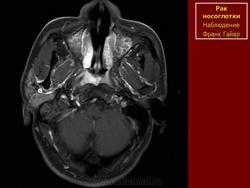

ЛОР. Онк. Рак носоглотки. +

Рак носоглотки